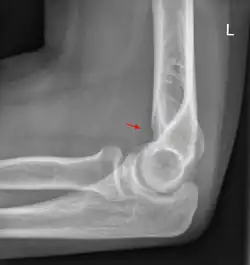

Fettpolsterzeichen

Das Fettpolsterzeichen ist ein Röntgenzeichen, welches zur Erkennung einer Fraktur bzw. einer okkulten Fraktur hilfreich sein kann.

Es handelt sich um die Darstellung von normalen anatomischen Fettpolstern an Gelenken als Aufhellungsband. Je nach Skelettregion sind diese Fettpolster beim Gesunden sichtbar oder nicht. Eine Verlagerung oder das Sichtbarwerden durch einen Gelenkerguss weist auf eine Fraktur hin.

Das bekannteste Fettpolsterzeichen ist das am Ellenbogen.